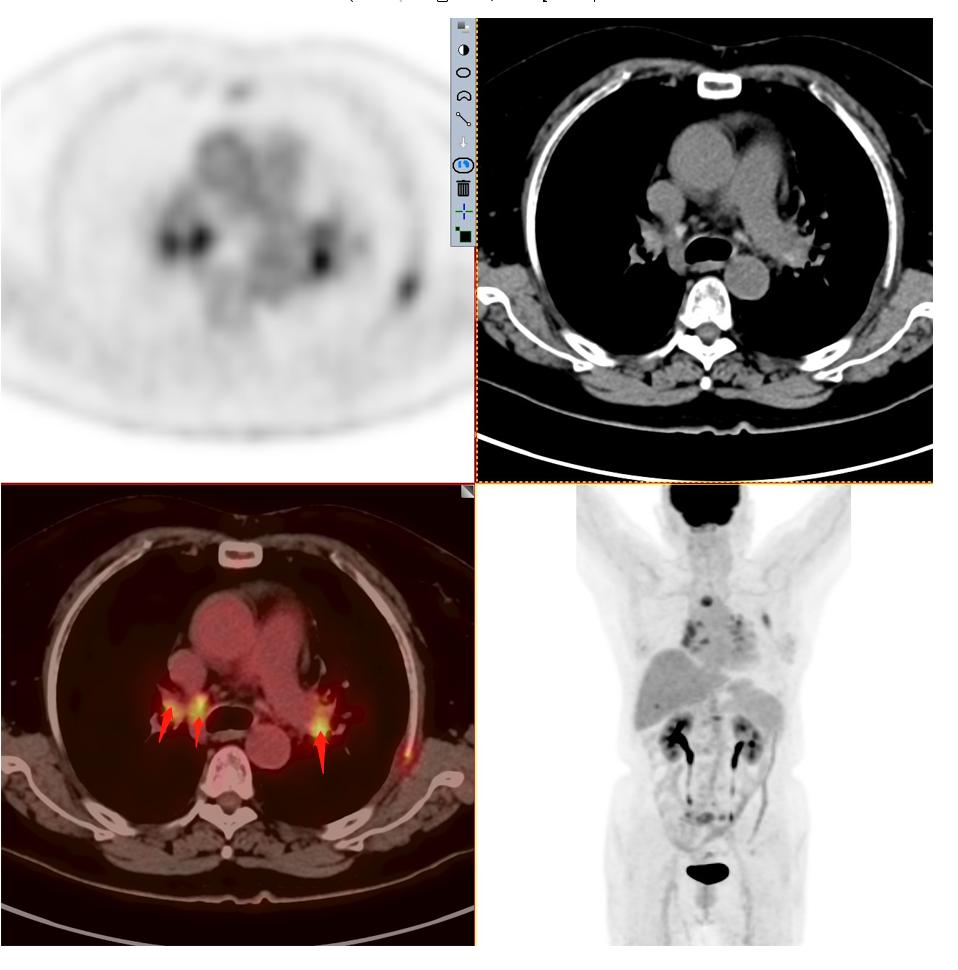

患者2:图3

发现纵隔多发淋巴结转移,并转移到对侧纵隔。

图4-5分别提示:胸骨、腰椎、骶骨及右侧髂骨骨转移。

因此该患者的肿瘤分期与第一位患者截然不同,同样病灶都在3cm以内,该患者属于T1cN3M1c 属于ⅣB期 最晚一期。这例患者当然不能手术了,只有寄希望于基因检测,如果有匹配的靶向药物,结合全身化疗或者免疫治疗,有一部分人还是有不错的效果。